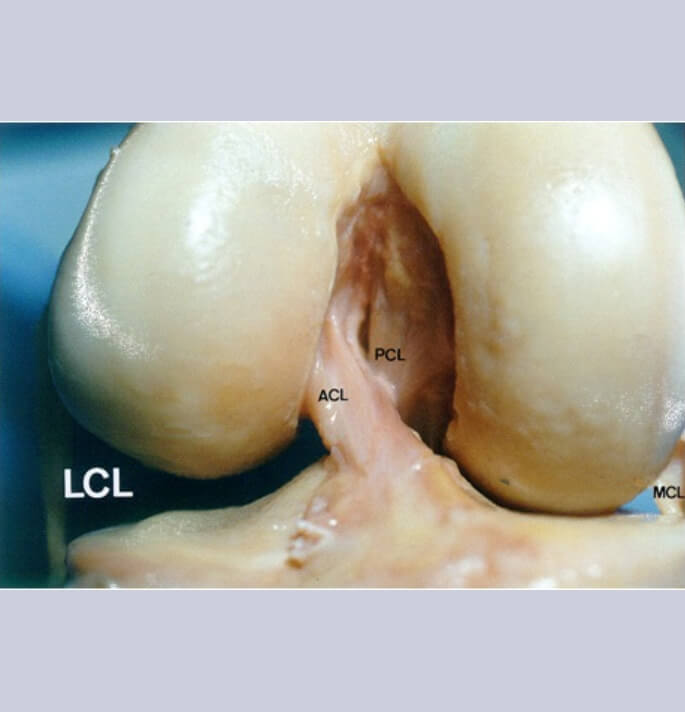

De belangrijkste steunende structuren (ligamenten) bestaande uit de

- Mediale band (mediaal collateraal ligament)

- Laterale band (lateraal collateraal ligament) dewelke buiten het gewricht (extra-articulair) zijn gelegen

- Voorste kruisband

- Achterste kruisband dewelke binnen het gewricht (intra-articulair) zijn gelegen

Deze structuren staan primair in voor de stabiliteit van de knie en begeleiden de knie tijdens de complexe plooi-strek activiteit welke gepaard gaat met een rotatiebeweging van het femur ten opzichte van de tibia